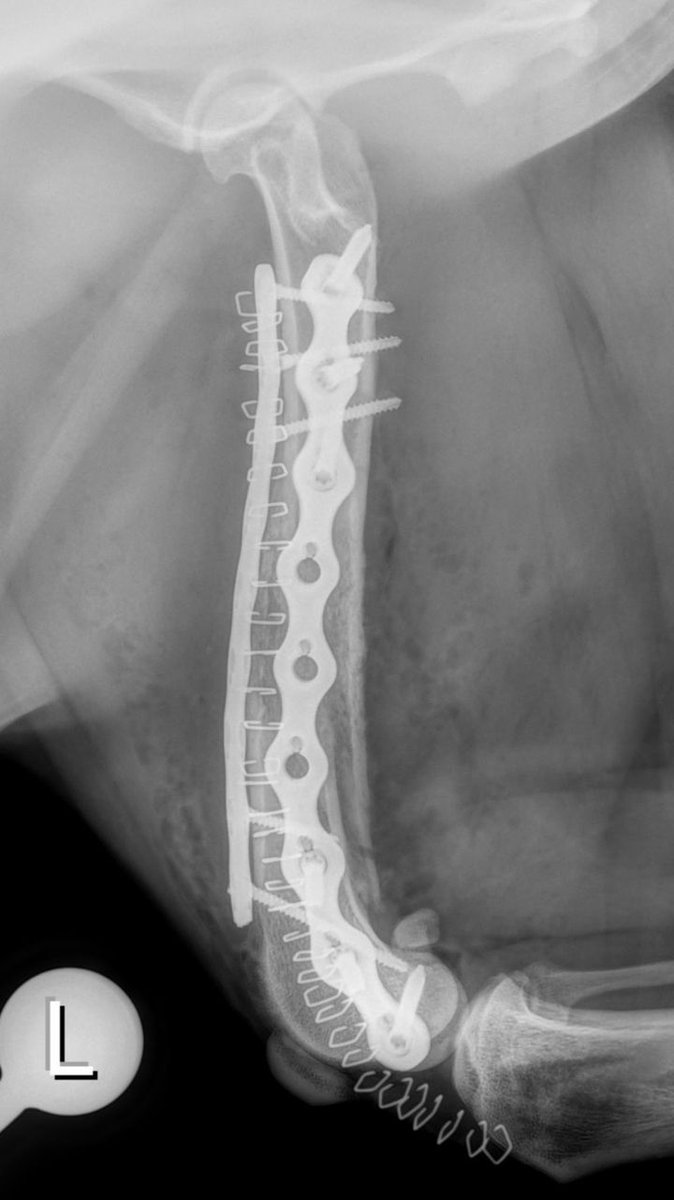

2 years

An exciting case requiring a team effort. Dr Massimo Petazzoni treated a displaced torsion fracture of the femoral shaft with two orthogonal biosurgex plates featuring our well-know, patented polyaxial locking mechanism. Read more on Facebook: https://t.co/lgUpJ9xUNL